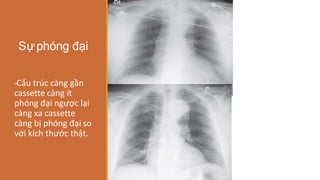

Sự phóng đại

-

‐Cấu trúc càng gần

cassette càng ít

phóng đại ngược lại

càng xa cassette

càng bị phóng đại so

với kích thước thật.